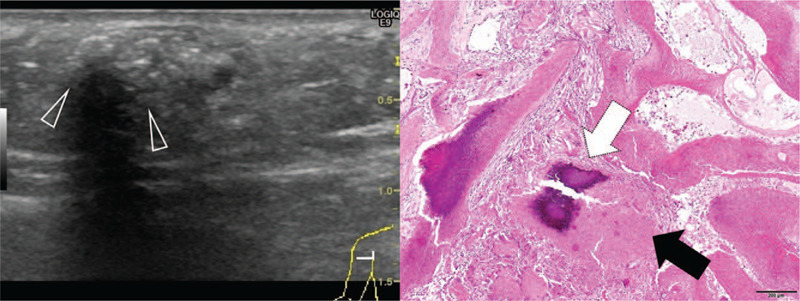

Figure 4.

Sonography of a 132-mo-old girl with a pilomatricoma located on the upper extremity. Scanning view of pathologic specimen is seen on the right panel. The duration of symptoms was 4 mo shows the absence of peritumoral Hyperechogenicity is absent, while calcification with posterior acoustic shadowing (arrowheads) is observed on transverse sonography. Therefore, calcification with acoustic shadowing was deemed to be present. Internal echogenicity was classified as grade 2: echogenic spot with posterior acoustic shadowing occupying <50% of the lesion's width. The pathological specimen shows the transformation of most basaloid cells into shadow cells. Dense calcium deposition is observed.